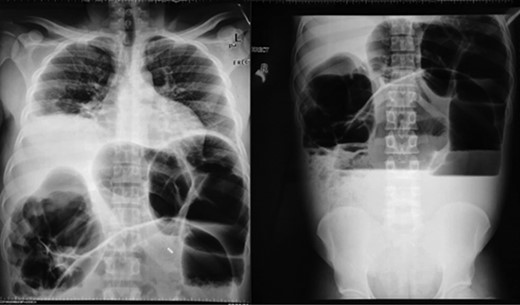

We present a 26-year-old male patient who presented at our accident and emergency department with complete bowel obstruction of 3 days’ duration. He presented with grossly distended abdomen, abdominal pains, vomiting and passing no flatus. The patient had no background history of chronic illnesses nor previous operations. On examination he was tachypnoic (24 bpm), his temperature was 38.5, heart rate was 68 and was peritonitic with a tense distended abdomen. Digital rectal examination revealed an empty rectum. His blood results revealed a potassium of 2.8 but the rest of his electrolytes and full blood count were normal. The erect chest and abdominal X-rays showed no air under the diaphragm and grossly distended large bowels with air–fluid levels (Fig. 1). A differential diagnosis of sigmoid volvulus was entertained after reviewing the X-rays. In view of peritonitis endoscopy was omitted and the patient was taken for an exploratory laparotomy after resuscitation. Intraoperative findings were a sigmoid volvulus and to our surprise a concurrent transverse colon volvulus with a non-distended cecum and collapsed small bowels. The sigmoid and transverse colon were redundant and their mesocolon had narrow parietal attachments. The involved segments were grossly distended and slightly dusky but pinked up after derotation (Figs 2 and 3). A subtotal colectomy and colostomy was performed and the surgical specimen sent for histopathology. The patient was discharged on the fifth day post operation and his recovery was uneventful. The histopathology results showed mucosal and submucosal congestion, chronic inflammation, compatible with volvulus and no malignancy or dysplasia was found. At 6 weeks’ follow-up clinic the patient was informed about the results.

Erect chest and abdominal X-rays showing dilated colon and air–fluid levels.